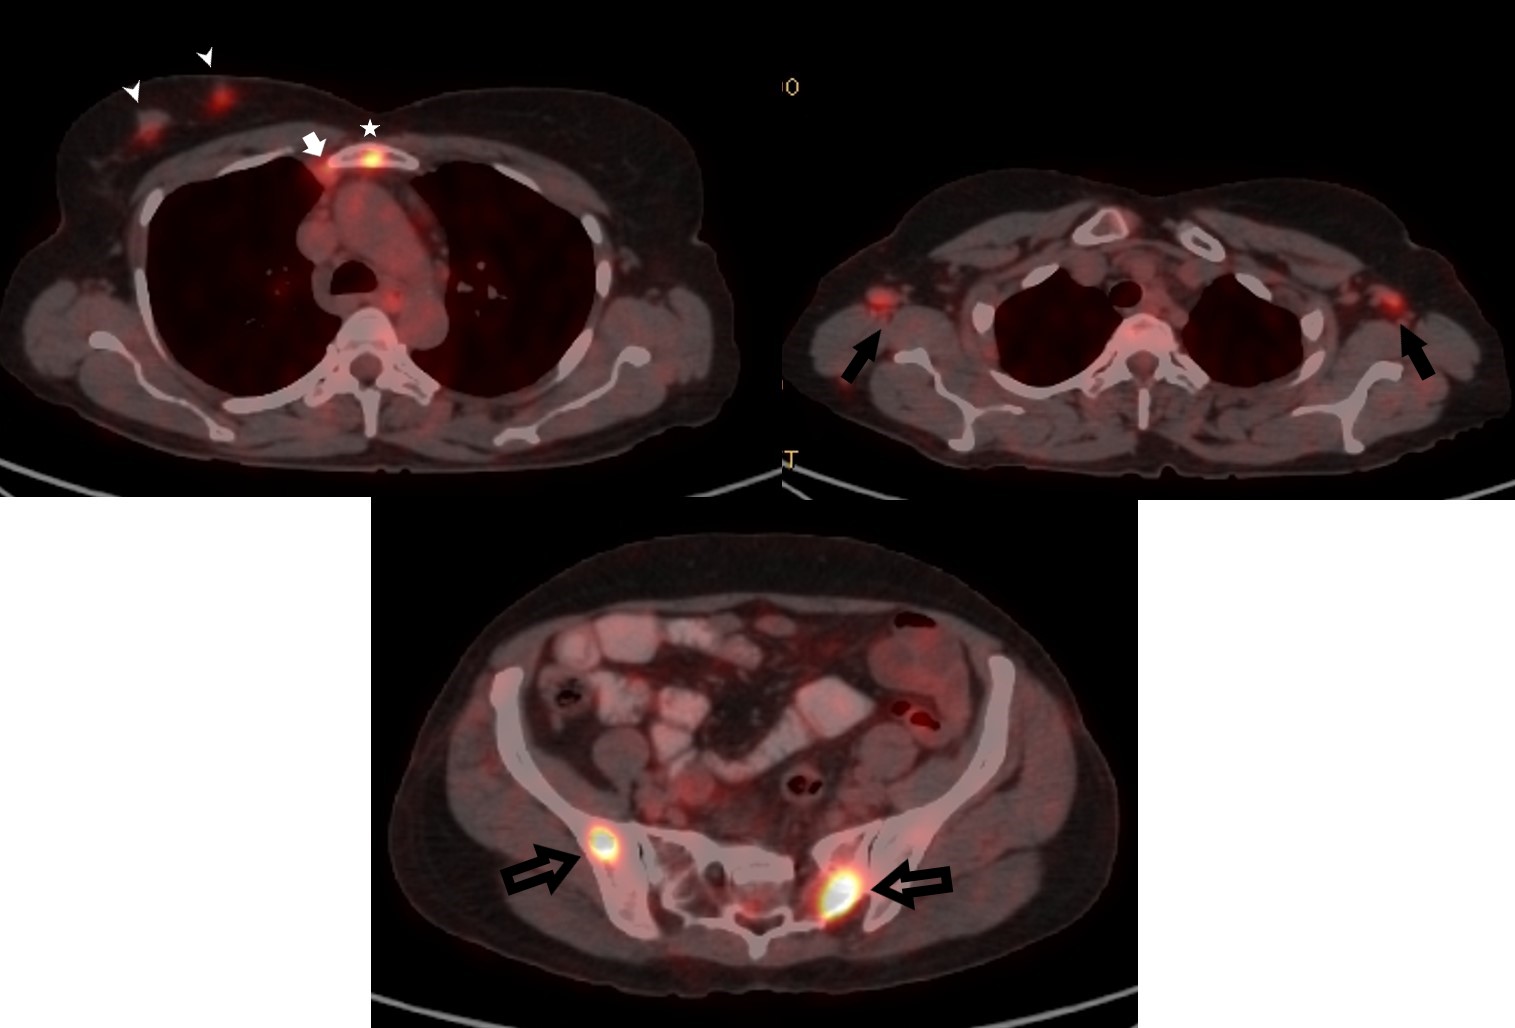

Findings Extremity X rays taken at the time of presentation to revealed lytic lesions in the metatarsal and the calcaneum. Subsequently she underwent a PET CT which revealed multifocal right breast lesions in the upper inner quadrant (White arrow heads) with right internal mammary node (white arrow) and sternal lesion (white star ).Bilateral axillary nodal uptake(solid black arrows)was seen along with multiple other lytic bony lesions (block black arrows ) Pre -biopsy Right mammogram (RCC) showed a larger spiculated and smaller irregular masses in the upper inner quadrant (Black arrow heads) .Axillary nodes showed diffuse cortical thickening on USG (black arrow),which were concerning for metastasis.Core biopsy specimen stained with H&E (x 400) demonstrated diffuse dense infiltration by lymphocytes, plasma cells and histiocytes. Emperipolesis- meaning phagocytosis of lymphocytes by histiocytes (Black arrow head) was seen in the samples.Immunohistochemistry revealed histiocytes demonstrating positivity for S100(x 400)